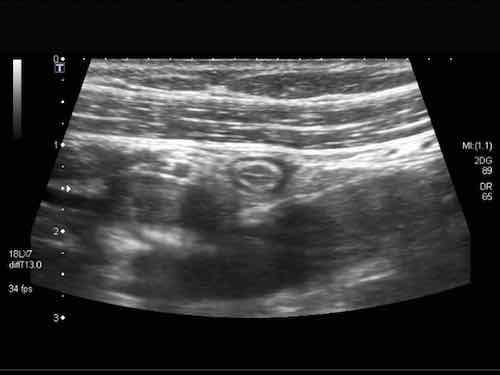

Đây là hình ảnh siêu âm của một trẻ 2 tuổi bị lồng ruột hồi manh tràng từng đợt, được khám trong khoảng thời gian giữa các cơn.

Hồi tràng với nhiều mảng Peyer sa vào manh tràng.

Hình ảnh siêu âm kinh điển của lồng ruột hồi-manh tràng ở hai trẻ khác nhau.

Trong cả hai trường hợp, đoạn hồi tràng bị lồng được định vị không đối xứng bên trong ống lồng ngoài, do mạc treo ruột tăng âm có chứa mỡ, bám vào hồi tràng và đi theo hồi tràng khi bị kéo vào trong.

Trong mạc treo, siêu âm cho thấy một hạch bạch huyết mạc treo (hbh) phóng đại ở cả hai.

Các hạch này phì đại như một phần của tình trạng tăng sản hạch bạch huyết toàn thân và khônghu trú trong lòng hồi tràng.

Do đó đây không phải là điểm dẫn đầu nguyên phát. Ở bệnh nhân bên phải, ruột thừa (mũi tên) cũng bị kéo vào trong.

Lưu ý cấu trúc đa lớp của thành bụng phía trước của phức hợp lồng ruột, đại diện cho ba lớp thành ruột bị gấp lại.